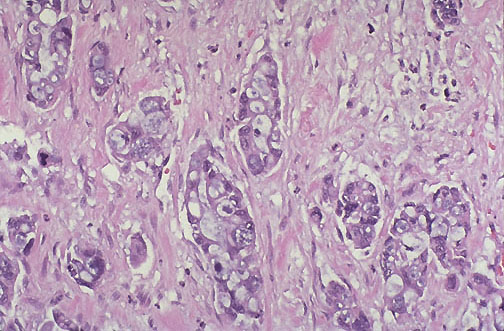

| At high magnification, this adenocarcinoma of the pancreas has very poorly differentiated glands and extensive desmoplasia (production of collagenous stroma). Typical mutations found in pancreatic adenocarcinomas include K-RAS (present in many adenocarcinomas), p16, p53 (present in many carcinomas), and SMAD4. |